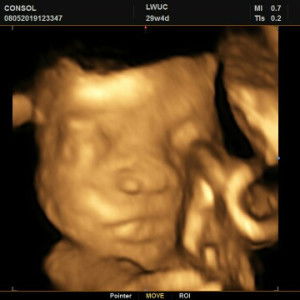

Normal po ba na magbleed po ung nose at nahhilo kapag buntis? 6 months napo buntis misis ko. Thankyou. or dahil din po sa init ng panahon?